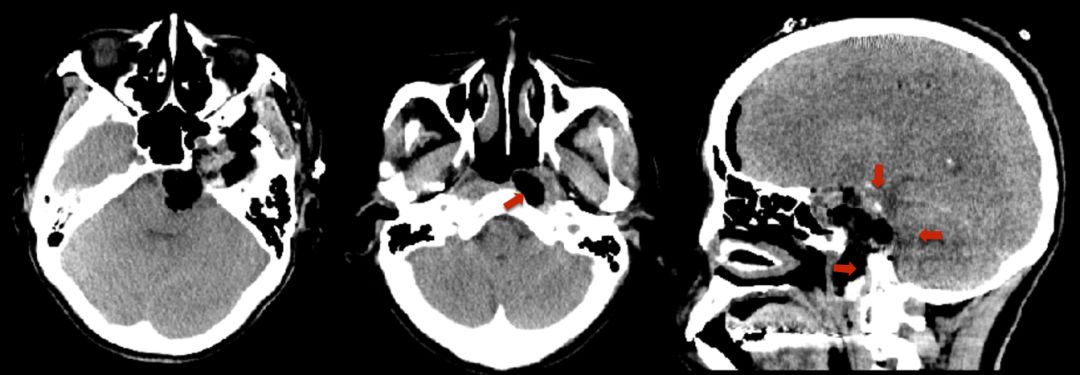

3. CT:左侧中颅窝、海绵窦、鞍区、咽后间隙稍低密度肿块,大小约65x48x40 mm,垂体及左颞叶受压移位。斜坡及左侧岩尖骨质受压吸收。

术前CT平扫